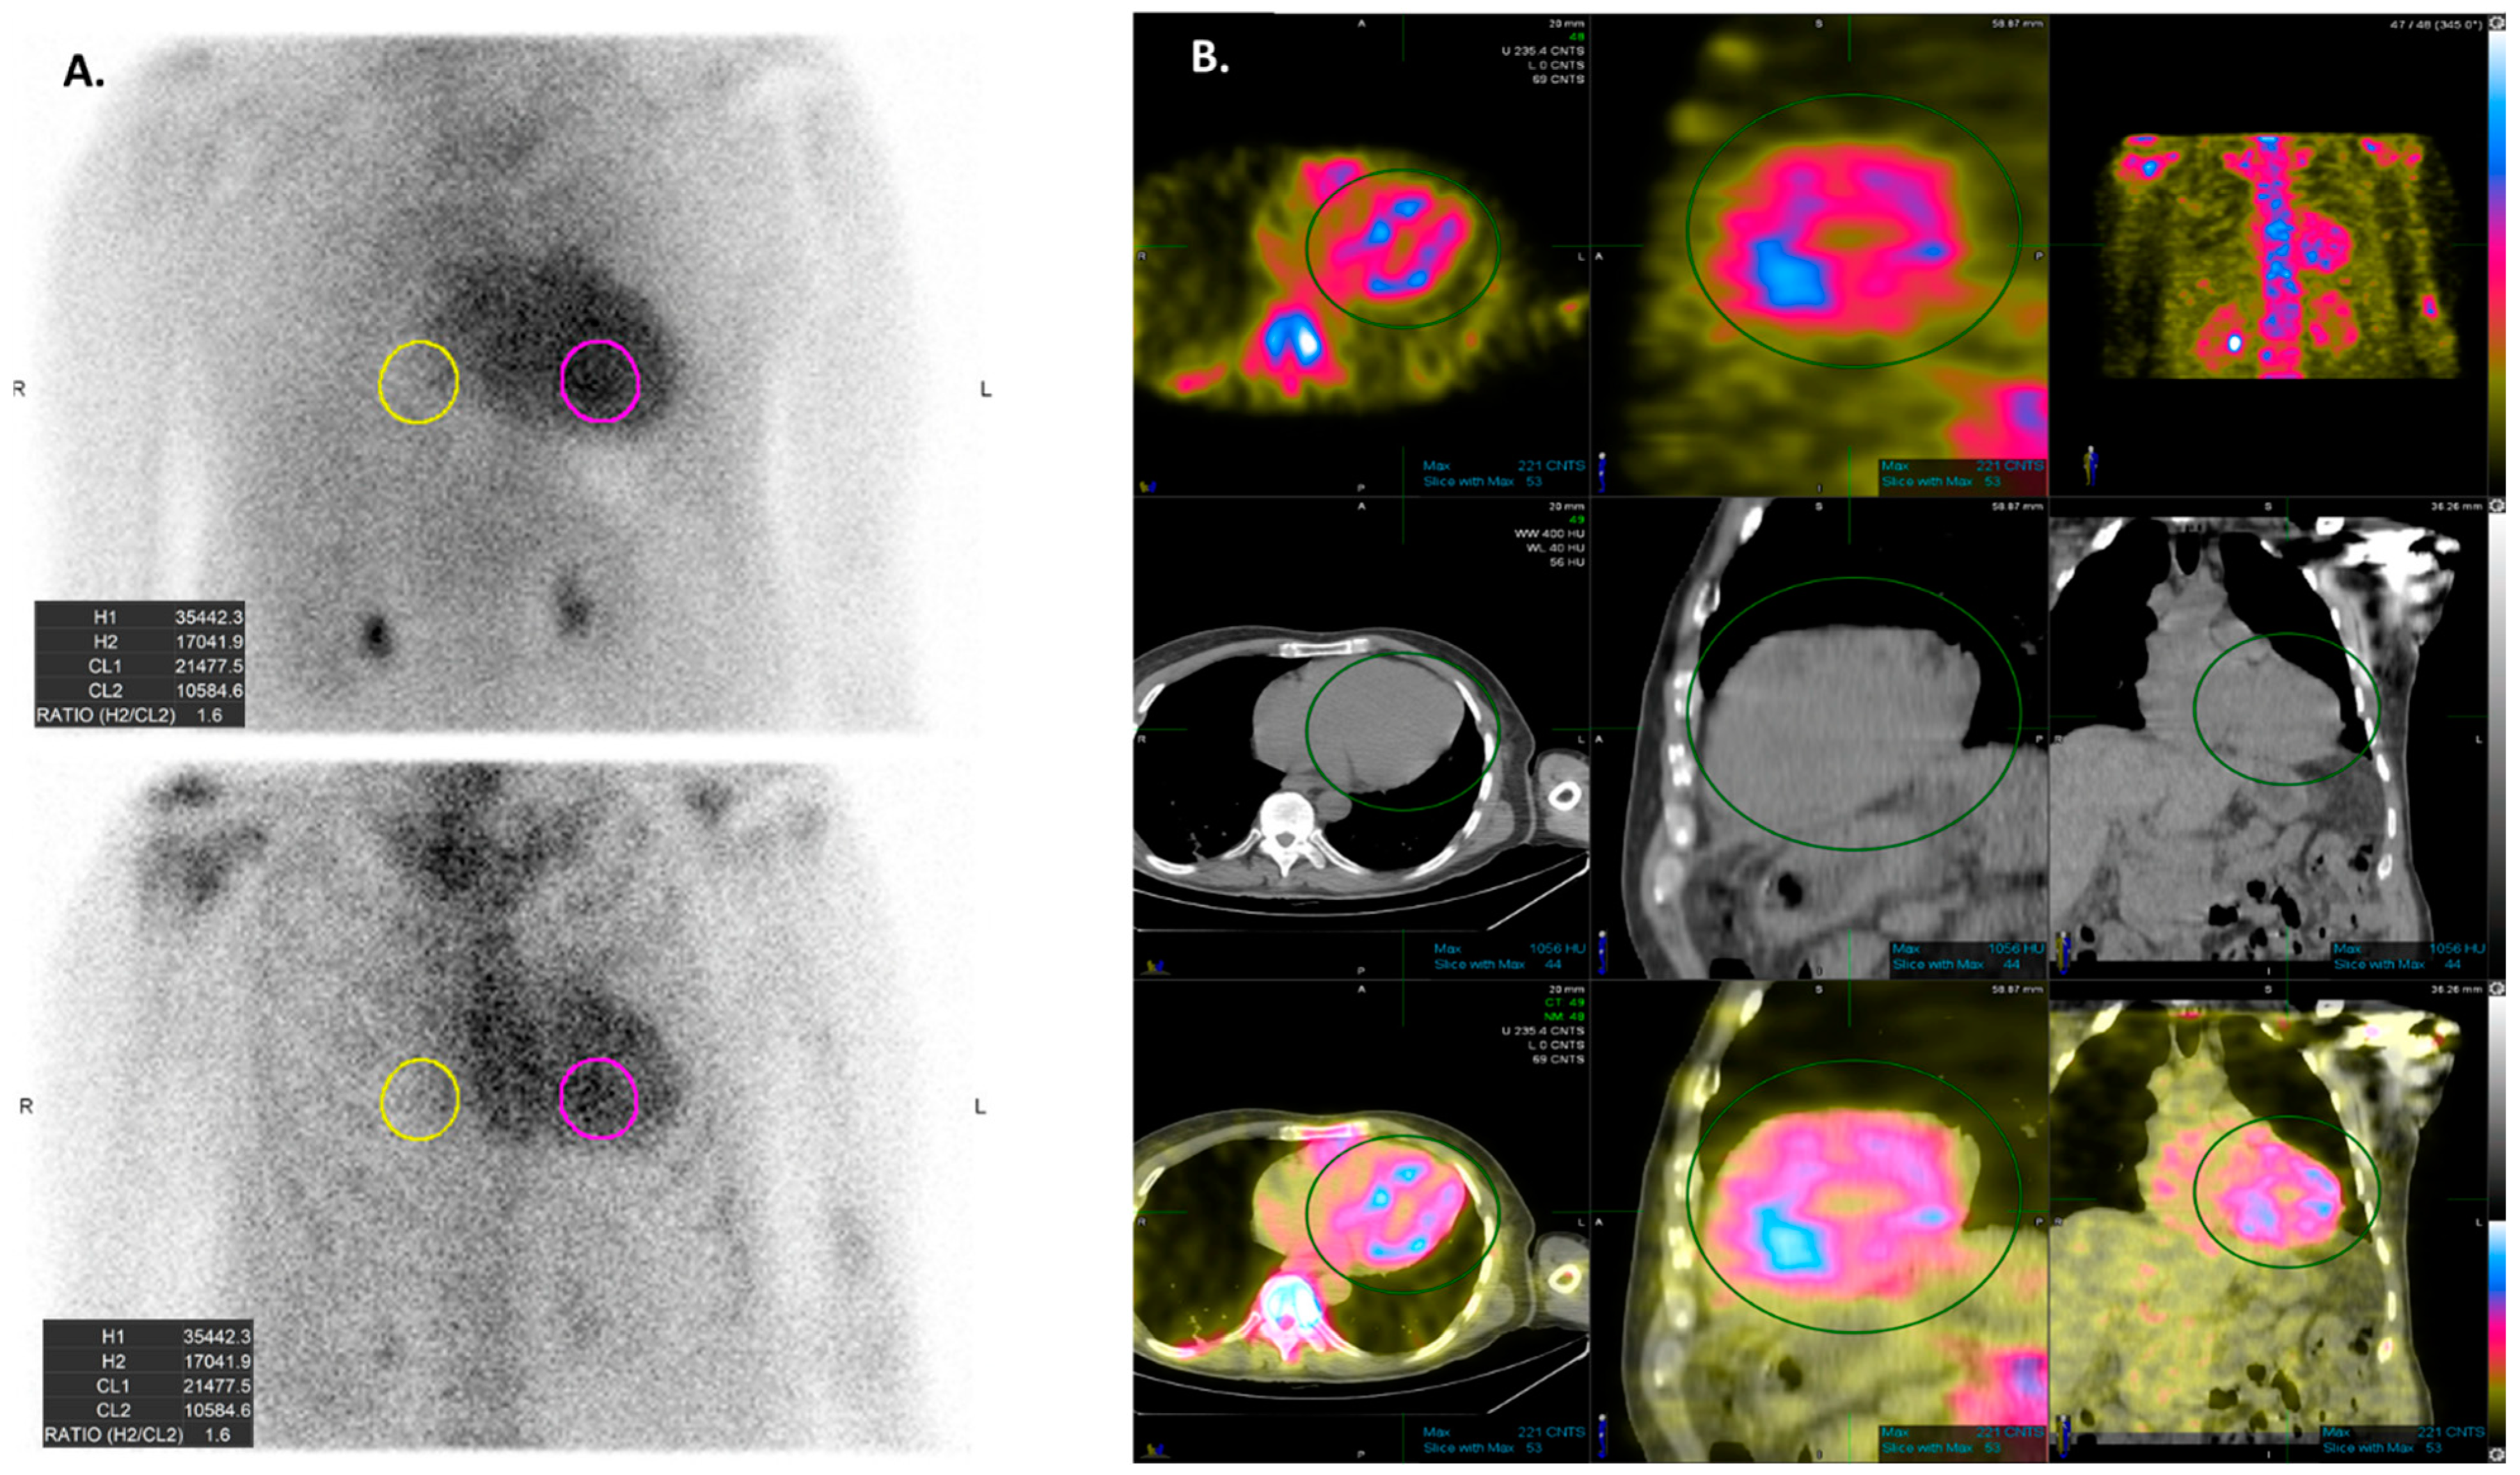

2. AI Applications to Electrocardiogram (ECG) in Cardiac Amyloidosis

3. AI Applications to Echocardiography in Cardiac Amyloidosis

- Goto, S.; Mahara, K.; Beussink-Nelson, L.; Ikura, H.; Katsumata, Y.; Endo, J.; Gaggin, H.K.; Shah, S.J.; Itabashi, Y.; MacRae, C.A.; et al. Artificial intelligence-enabled fully automated detection of cardiac amyloidosis using electrocardiograms and echocardiograms. Nat. Commun. 2021, 12, 2726. [Google Scholar] [CrossRef] [PubMed]

- Cotella, J.I.; Slivnick, J.A.; Sanderson, E.; Singulane, C.; O’Driscoll, J.; Asch, F.M.; Addetia, K.; Woodward, G.; Lang, R.M. Artificial intelligence based left ventricular ejection fraction and global longitudinal strain in cardiac amyloidosis. Echocardiography 2023, 40, 188–195. [Google Scholar] [CrossRef] [PubMed]